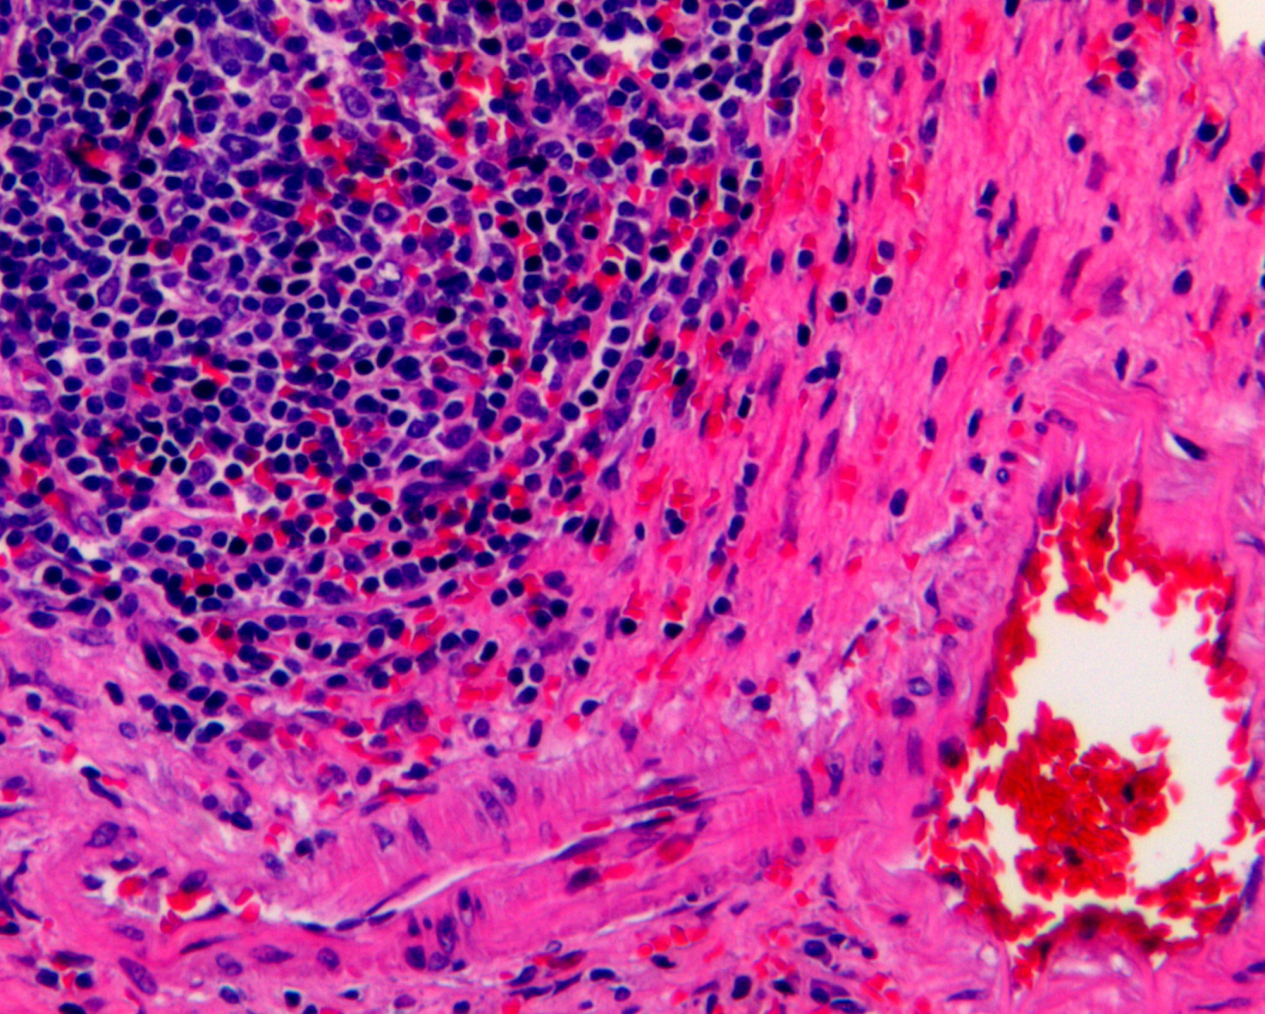

H&E STAINS

top